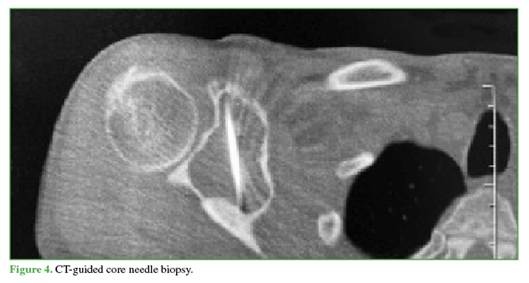

A CT-guided core needle biopsy was performed to maximize diagnostic yield and obtain a representative sample of the lesion5 (Figure 4). Pathology reported a grade II chondrosarcoma.